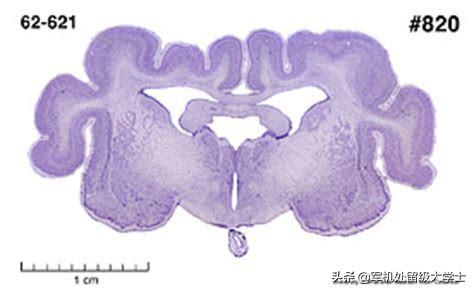

Cette photo est très révélatrice de la taille des cochons d'Inde.